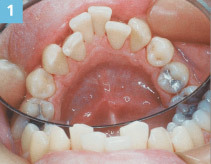

torus palatinus

-exophytic growth of normal compact bone -more common in females and native americans -genetic